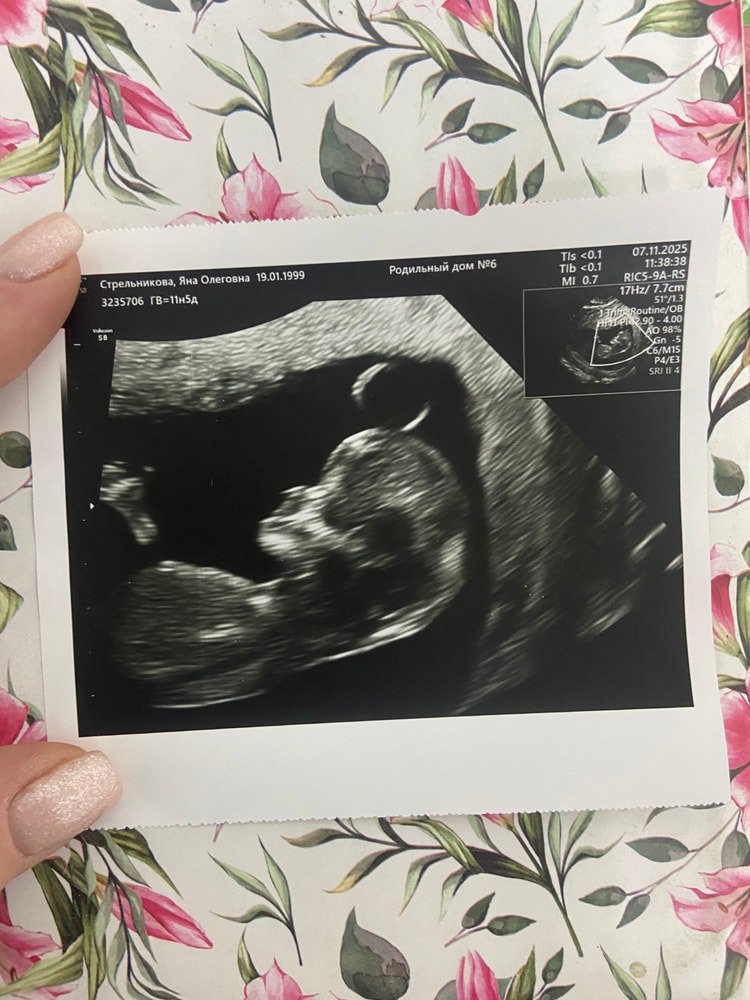

Вчера узи показало девочку 15.5 недель

Вот наша близкая встреча с тобой 😍

по ктр 52 мм 11.6 недель